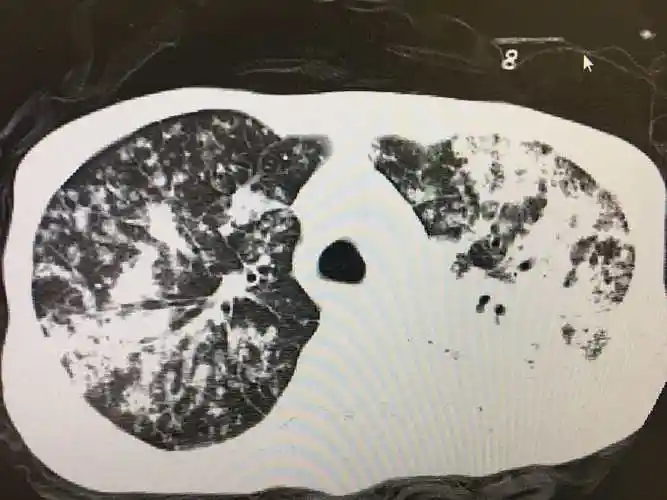

南京江北医院成功治愈难治型肺结核患者